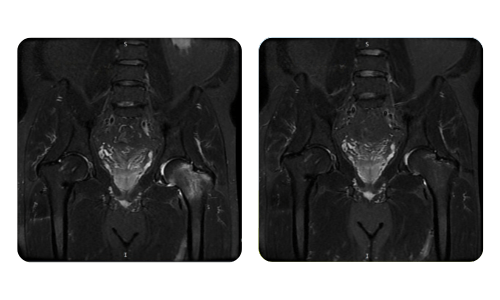

Progresul pacienților noștri, măsurat înainte și după terapia hiperbară, reflectă eficiența și impactul pozitiv al tratamentului. Descoperă rezultate documentate ale terapiei hiperbare la clinica Hyperbarium Oradea, bazate pe evaluări clinice și date obiective care evidențiază îmbunătățiri semnificative în diverse afecțiuni.